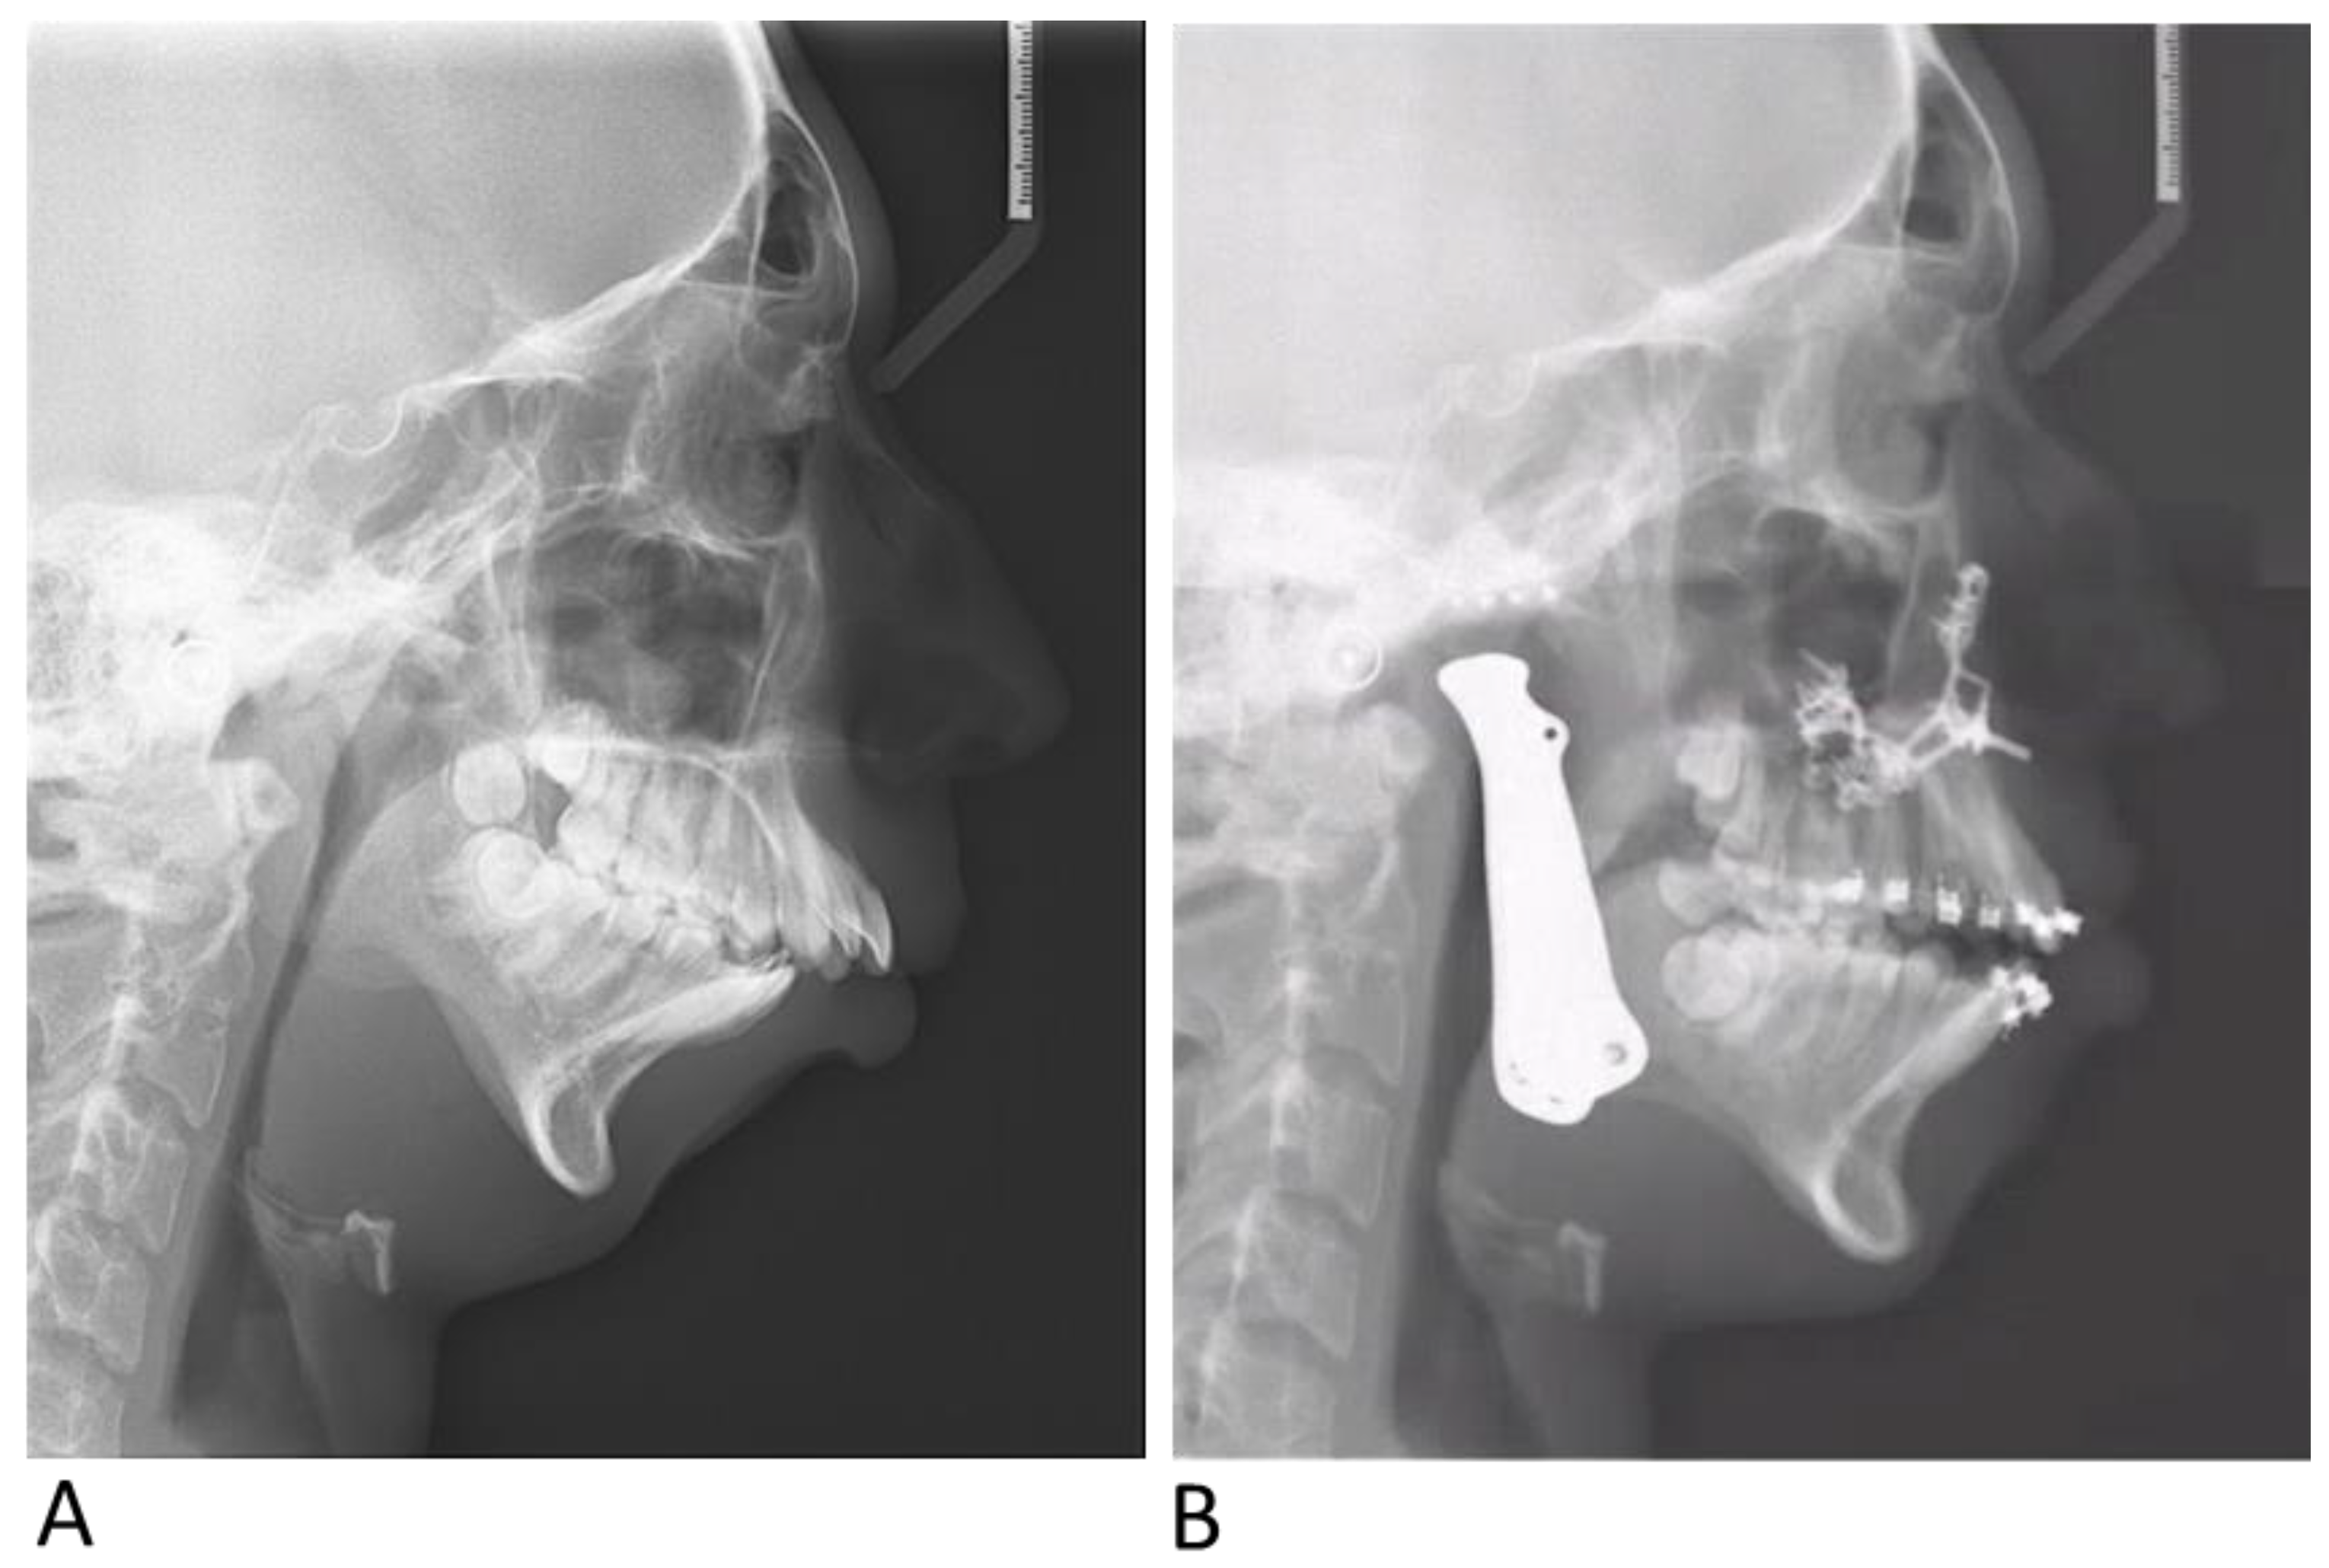

2.3.3. Outcome Evaluation